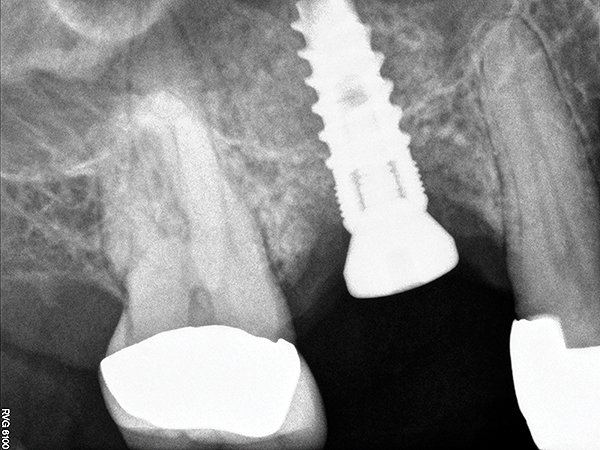

The implant is then delivered and should be well stabilized in the bone. If there is any mobility of the implant, it can either be placed a little deeper (if there is enough native bone) or the implant can be removed and the procedure aborted, in which case it would be a two-stage procedure. This should rarely occur with the tapered designed implant, even with only 2 mm of native bone. Using a bone-level platform-shifting implant (or a tissue-level designed implant) is critical, as the hard and soft tissue will establish a biologic width. If an external hex type of implant is used and the shoulder is placed at the bone level, an expected bone loss of 1.5 mm to 2 mm will occur.24 Figure 10 shows proper bone-level implant depth placement with a platform-shifting design. In this case, a 3-mm healing abutment was placed at the time of surgery to avoid a secondary uncovering surgery, but an implant-level healing abutment could have been placed instead. As can be seen, there was only about 2 mm to 3 mm of native bone height. The membrane was raised about 8 mm to 9 mm. Comparing the radiograph on the day of surgery (Figure 10) to the 6-month postoperative radiograph (Figure 11) shows no loss of native bone, as well as the positive change in appearance of the grafted bone. The 3.5-month CBCT scan (Figure 12) shows good healing of the bone with no coronal bone loss. With minimal native bone present, as in this case, the use of a non-platform-shifting or non-tissue-level implant design could be problematic. After 1.5 mm to 2 mm of crestal bone loss, an external hex designed implant could develop instability with possible implant failure. If a non-tapered implant is used and bone loss occurs during healing, migration of the implant into the sinus could potentially occur. The surgeon can use either a healing abutment or implant-level closure screw over the implant shoulder. With patients who tend to use their tongues to explore or play with the area, or if the area is under a removable partial denture, a closure screw is recommended.

Fig 10. Radiograph of implant No. 3 and sinus augmentation, day of placement. There is about 2 mm to 3 mm of native bone, and the sinus has been raised about 8 mm to 9 mm.

Figure 10

Fig 11. 7-month postoperative radiograph of the restored implant No. 3.

Figure 11